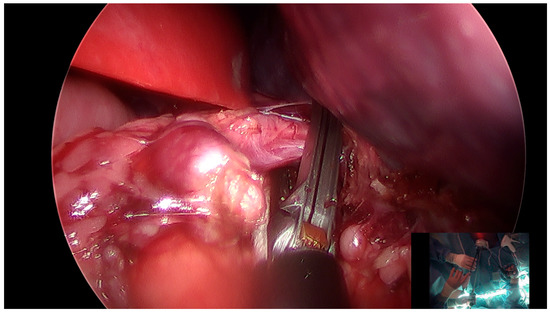

2.1. Case 1: SIPES-Assisted Mesenteric Lymphatic Cyst Excision with Ileocecectomy and Primary Anastomosis

2.2. Case 2: SIPES Splenectomy and Cholecystectomy

2.3. Case 3: SIPES Distal Pancreatectomy with Splenectomy